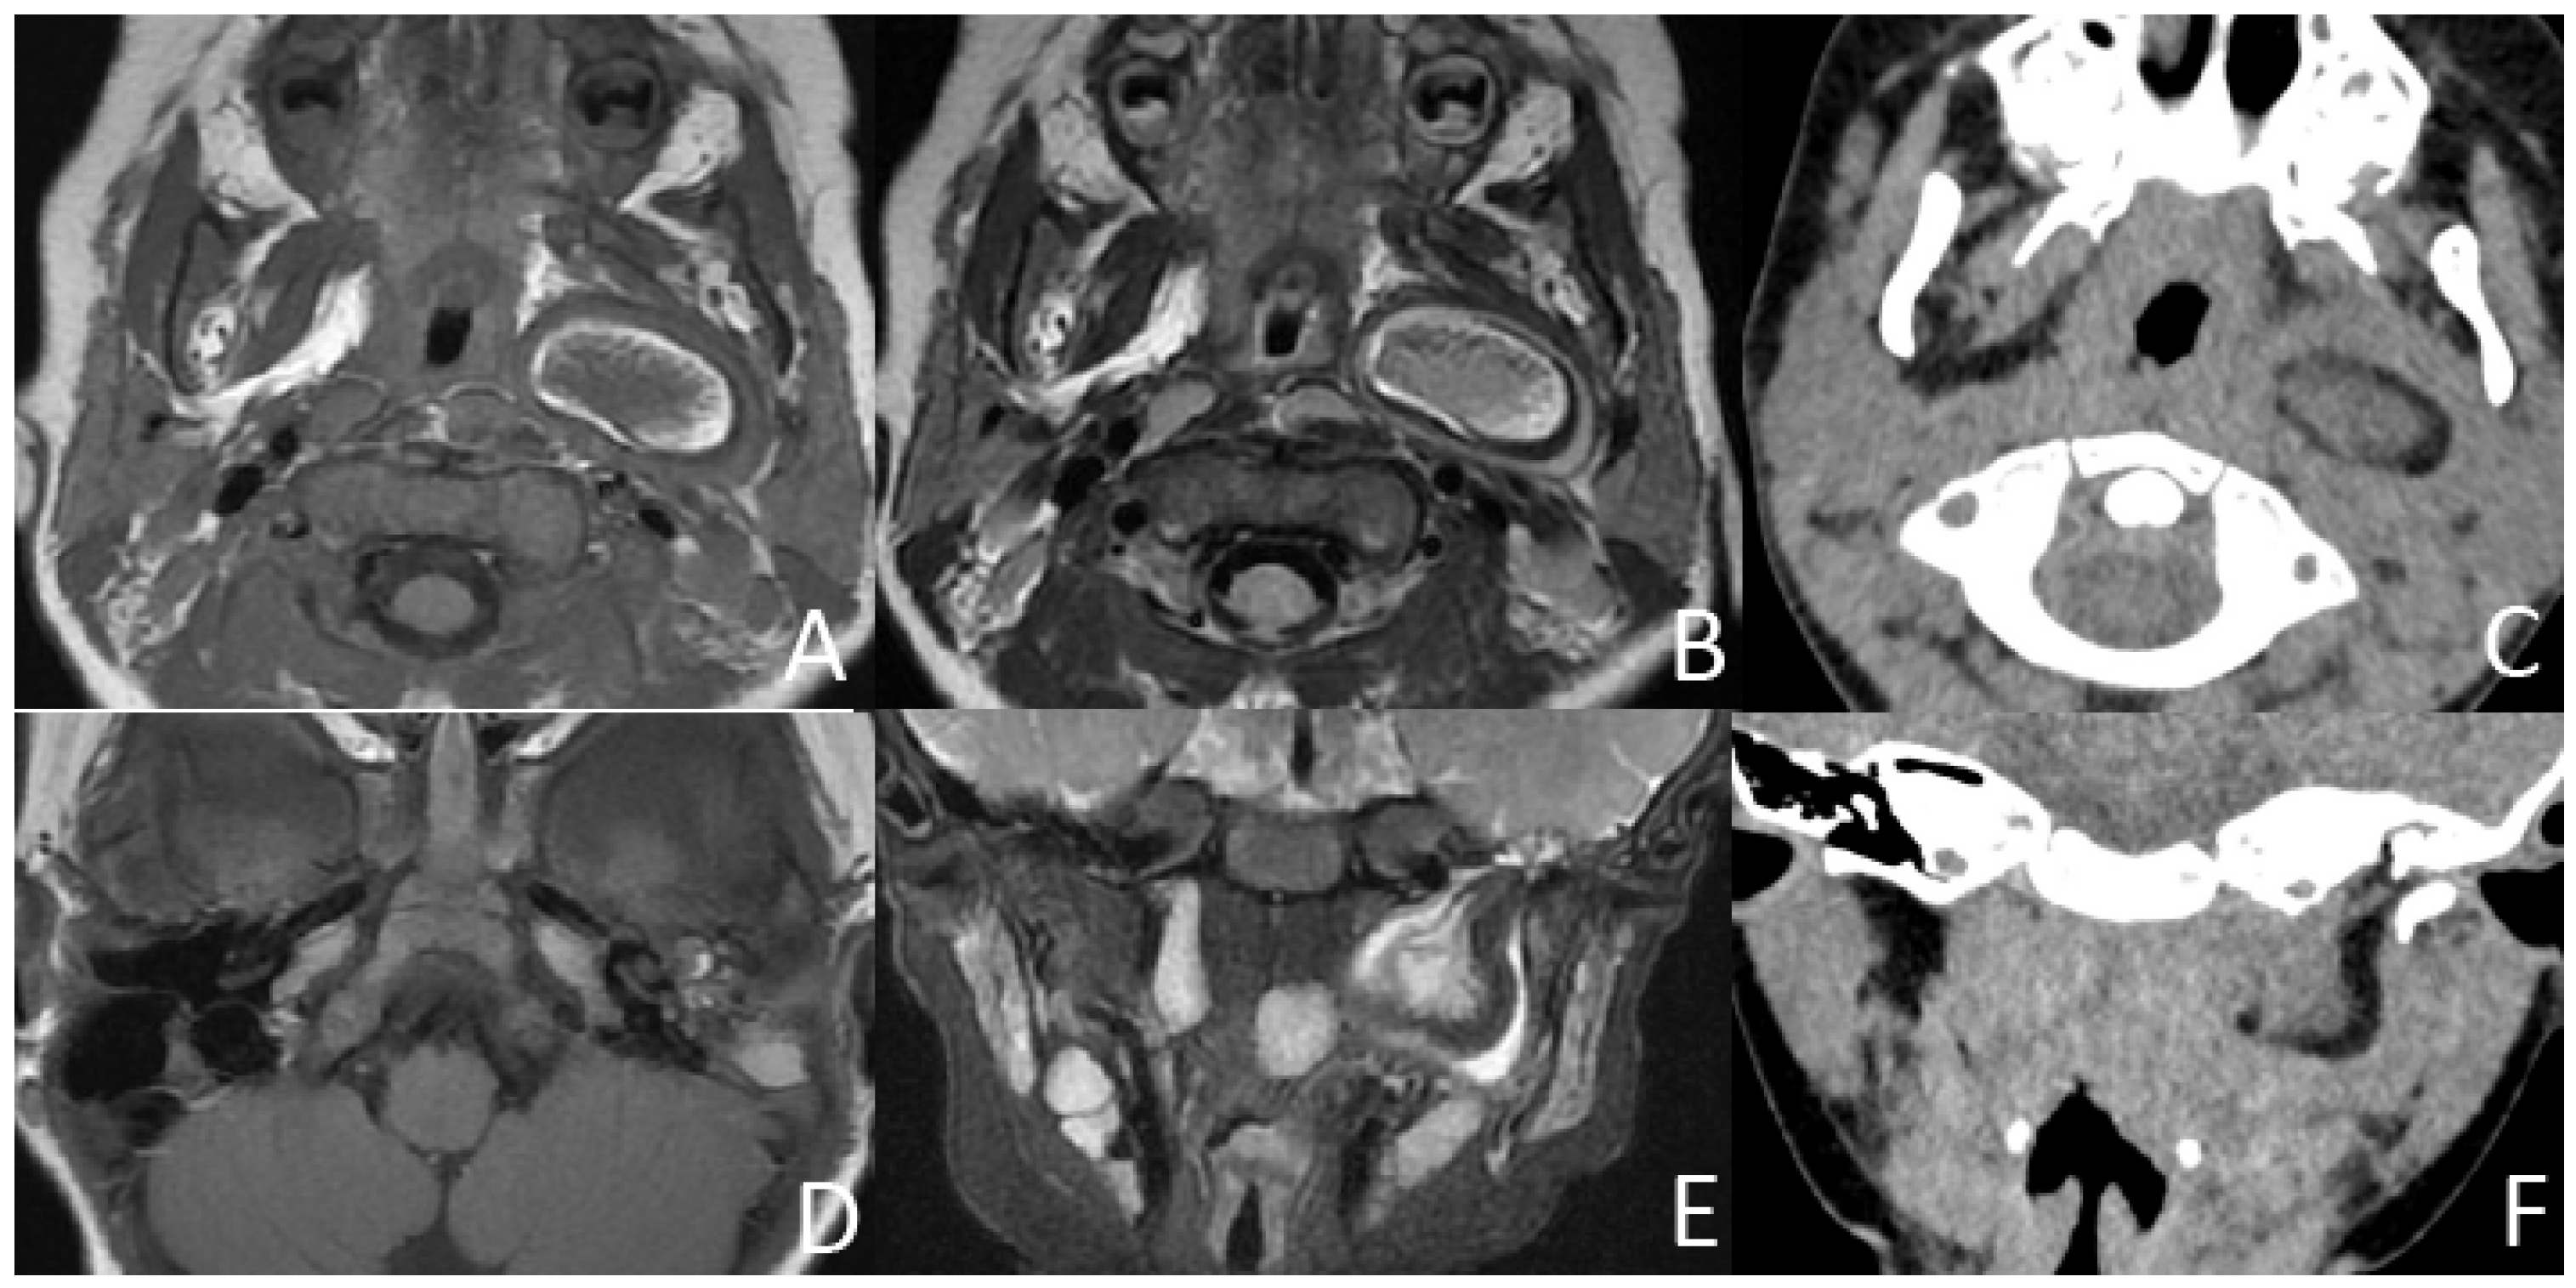

Figure 4. MRI (conducted at 11 months) and CT (conducted at 2 years and 7 months) of a girl who failed newborn hearing screening of the left ear, presenting with left otopyorrhea from 2 years old. (A,B) Axial T1-weighted, T2-weighted MRI show a multilayered circumferential mass in the left parapharyngeal space that is soft tissue, lipid, fibrous capsule, and soft tissue intense from inside to outside. (C) Axial CT shows a 3-layered circumferential mass that is soft tissue dense, fat dense, and soft tissue dense from inside to outside. (D) Axial T1-weighted MRI shows an irregular hyperintense and isointense mass in the left middle ear. (E,F) Coronal T2W-SPIR MRI and CT show the pear-like multilayered circumferential mass in the left multilayered circumferential mass with the pedicle extending to the left middle ear and the bone defect of the inferior wall of the external auditory canal and mastoid process.

In addition, three (21.4%) cases presented with irregular shapes the MRI or CT findings that were atypical. One case presented with a sausage-like mass in the right nasal vestibule and nasal limen that was mainly high-signal with multiple filament-like low signals inside on T1-weighted and T2-weighted MRI (Figure 3). One case presented with a multilayered circumferential mass in the left parapharyngeal space that was soft tissue, lipid, fibrous capsule, and soft tissue intense from inside to outside, and the mass extended to the left external auditory canal and middle ear (Figure 4). One case presented with irregular fat and soft tissue density mass originating from the back side of the left soft palate (Figure 5).

3.3. Associated Malformation

However, there were three cases whose imaging findings were atypical. All masses contain fat and soft tissue, but their distribution and proportions vary. In rare cases, the mass has a thick capsule.